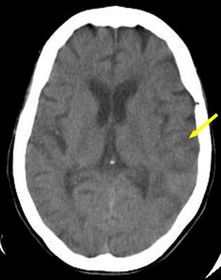

Tomografía computarizada Es una escanografía que crea una serie de imágenes en cortes transversales a rayos X de la cabeza y del cerebro. También se le llama tomografía axial computarizada o “CAT scan.” (1)